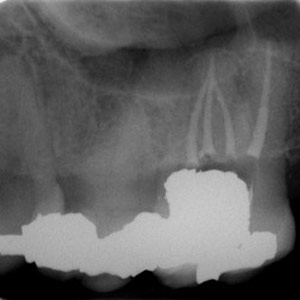

NON-SURGICAL

Oftentimes, our patients need non-surgical treatments that require minimal intervention. This intertwines with our belief that preventative maintenance and regular dental care can minimize the need for surgeries. You can rest assured that our highly trained and experienced team consistently provides the highest quality endodontic treatments and assistance available in the North Shore.